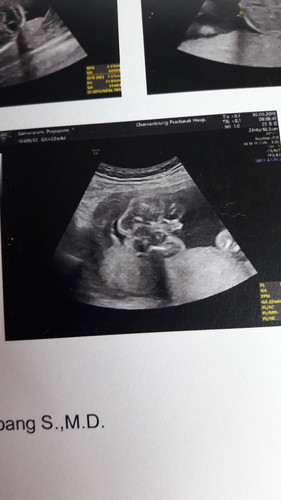

ไม่มั่นใจว่าชาย/หญิงค่ะ

ช่วยดูหน่อยค่ะใช่ผู้ชายไหมค่ะ

หมอว่าไงคะ มองไม่เห็นเลยค่ะ

ดูไม่ออกค่ะแม่ 555